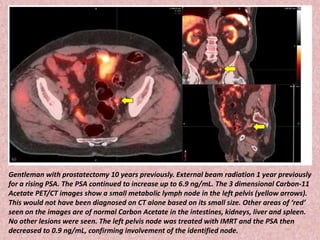

Gentleman with prostatectomy 10 years previously. External beam radiation 1 year previously

for a rising PSA. The PSA continued to increase up to 6.9 ng/mL. The 3 dimensional Carbon-11

Acetate PET/CT images show a small metabolic lymph node in the left pelvis (yellow arrows).

This would not have been diagnosed on CT alone based on its small size. Other areas of ‘red’

seen on the images are of normal Carbon Acetate in the intestines, kidneys, liver and spleen.

No other lesions were seen. The left pelvis node was treated with IMRT and the PSA then

decreased to 0.9 ng/mL, confirming involvement of the identified node.